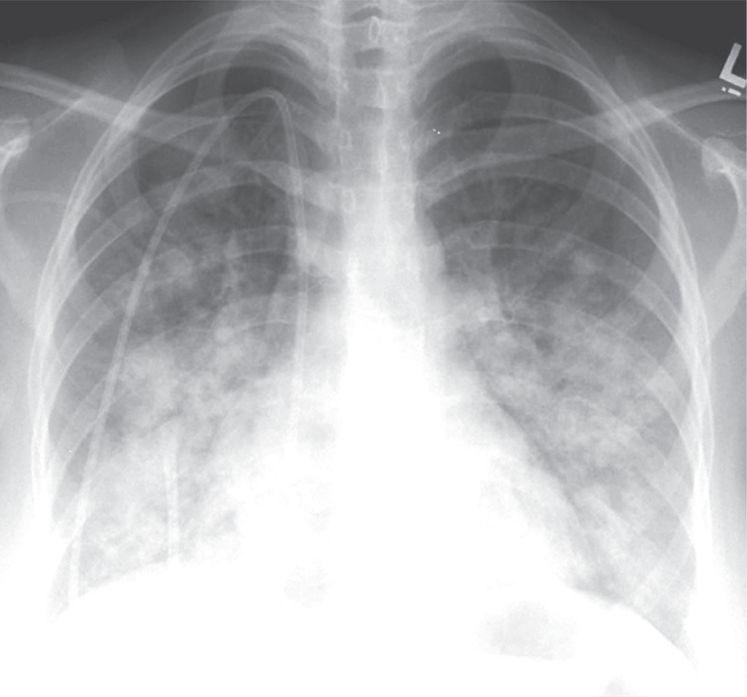

肺的均匀致密影是肺泡内气体完全被代替的结果。实变的肺内血管是不可见的(图2-1A)。

图2-1 实变:均匀致密影,纹理遮盖,空气 支气管征和CT 血管造影征

A.肺水肿所致的右肺实变。可见双侧实变肺内空气支气管征,肺血管模糊;B. 右肺中下叶肺炎患者增强CT 显示病变区均匀实变,肺体积保持不变,空气支气管征( 黑色箭头) 和致密血管影( 白色箭头),其密度高于邻近实变肺组织( 即“CT血管造影”征)